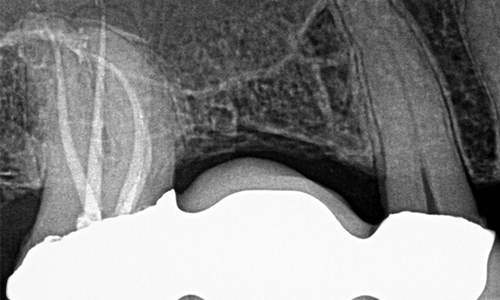

Case Study: Endodontic Retreatment of Periapical Lesion. September 5, 2024

Dr. Sameer Jain’s case study details how to retreat an extensive periapical lesion by locating a missing MB2 canal to resolve a chronic infection and alleviate patient symptoms.